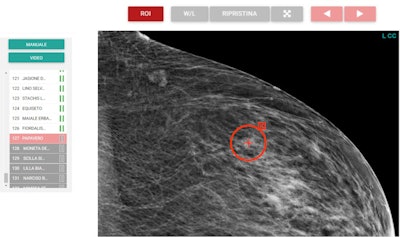

![Region-of-interest delineation in a magnified craniocaudal projection. No more than one region of interest can be placed on each projection. If a case is left with a region of interest placed on a mammographic projection, it will be classified as true positive if the region of interest matches the one previously delineated during dataset building for the actual presence of carcinoma; otherwise, the case will be classified as a false positive. To store the case as a negative one and move on to the next one, the reader can click on the button with white arrowheads on green background (shown at the right end in top figure [Example of mediolateral oblique projection magnification]). The case will be classified as true negative if carcinoma is not actually present, otherwise as a false negative.](https://img.auntminnieeurope.com/files/base/smg/all/image/2021/09/ame.2021_09_10_19_02_6235_2021_09_13_womens_insider_Figure3.png?auto=format%2Ccompress&fit=max&q=70&w=400)